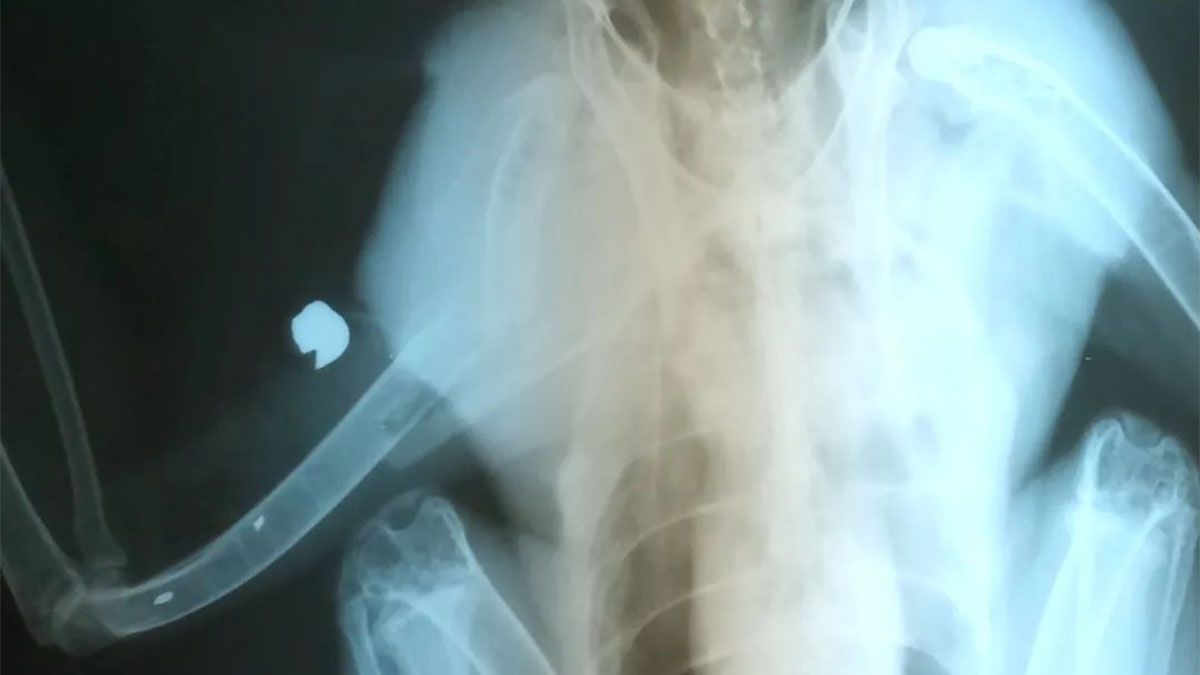

Un gavilán mixto baleado con un aire comprimido en Guaymallén se recupera de la fractura que sufrió en una de sus alas. Está bajo los cuidados de la Fundación Cullunche, donde le sacaron un balín de 5,5 centímetros que entró por su pecho y salió por su ala, lo que le provocó la lesión. Ahora está en una jaula exterior junto a otros gavilanes y comienza la rehabilitación para intentar volar nuevamente.

Luego de la cirugía que le hicieron para limpiar y sacar el balín de aire comprimido con el que le dispararon a principios de abril en Guaymallén, el ave estuvo en un recinto pequeño para que se moviera lo menos posible, y así garantizar su reposo para soldar la fractura que sufrió.

gavilan mixto baleado guaymallen balines extraidos.jpg

La Fundación Cullinche recibe casi a diario aves que fueron baleadas.